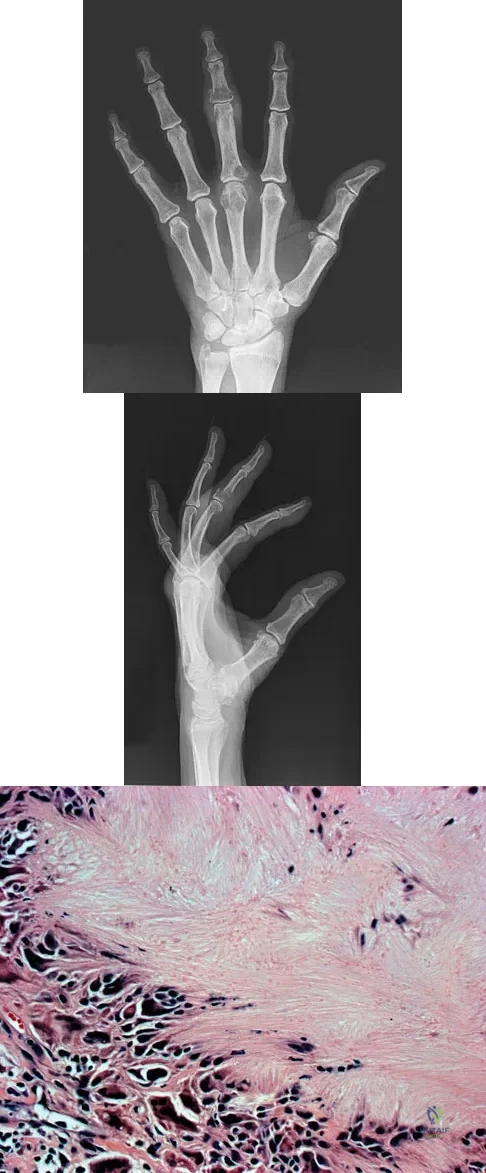

Question 20

An 83-year-old woman reports pain in her left middle finger after a minor injury. Laboratory studies show a WBC count of 7,000/mm3, an erythrocyte sedimentation rate of 3 mm/h, a uric acid of 10.4 mg/dL, and a normal serum protein electrophoresis. Radiographs are shown in Figures 49a and 49b. A core biopsy specimen is shown is Figure 49c. In addition to treatment of the finger fracture, treatment should include

Explanation